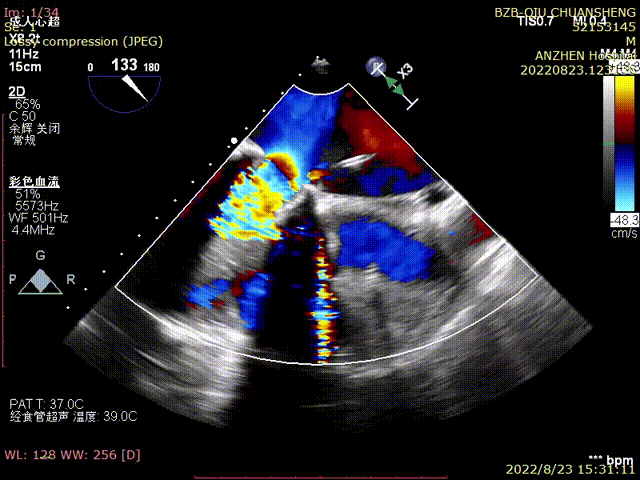

TTE-各大瓣膜反流(CDFI)

TTE-左室长轴-二尖瓣生物瓣+主动脉瓣生物瓣(CDFI)